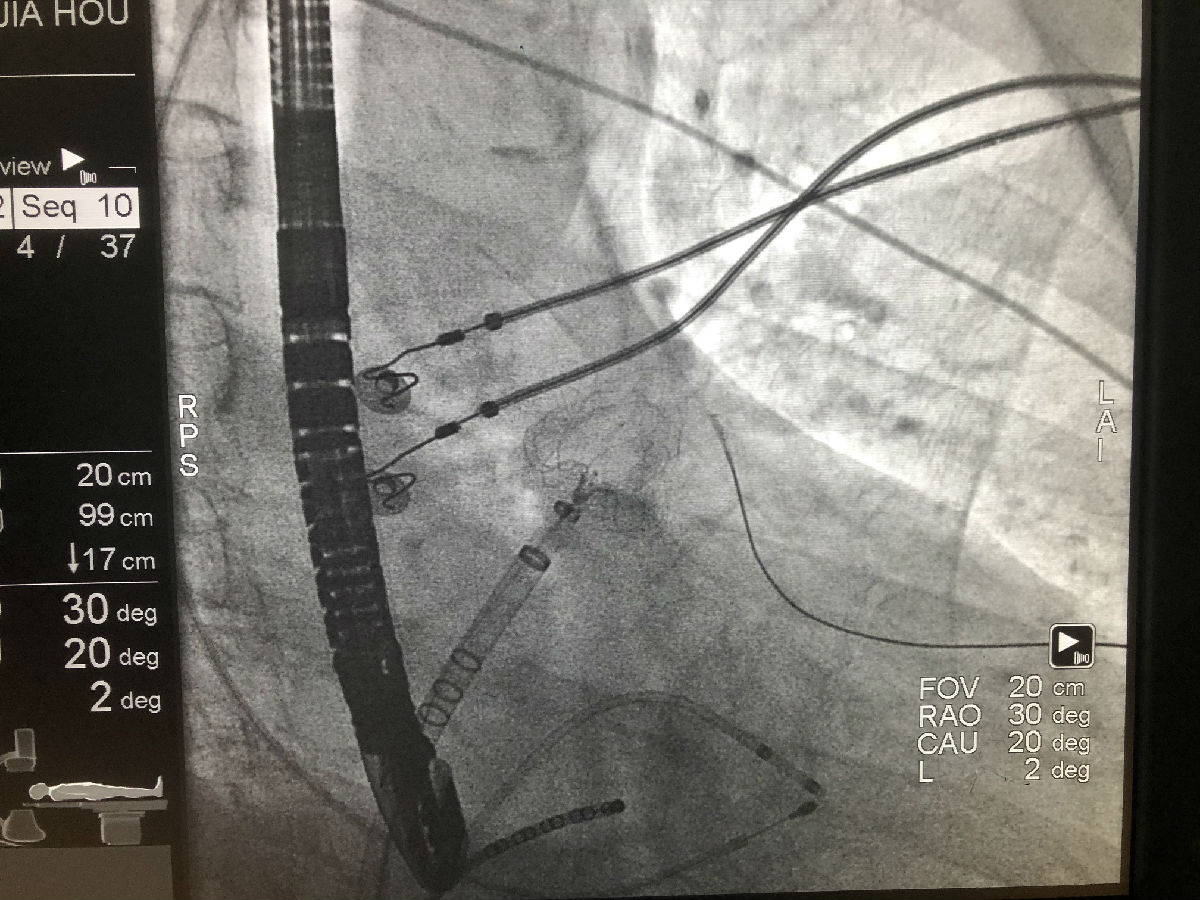

2022年6月15日,在肖骏副院长的带领下,李传伟、汪浩、冉阳、徐刚医师等心内科电生理及结构性心脏病团队共同协作,在超声科、麻醉科、影像科的配合下成功完成房颤射频消融+左心耳封堵一站式手术。术中克服左房偏大、心耳轴向欠佳等困难,成功完成肺静脉电隔离及左心耳的封堵,术中术后超声验证封堵器稳定,无残余分流。